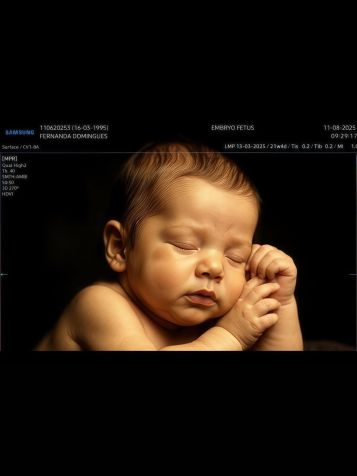

A empresária Fernanda Stroschein, 28, a noiva do funkeiro MC Guimê, 32, compartilhou um novo ultrassom da filha e surpreendeu os internautas ao exibir detalhes do rostinho da bebê em resolução 8K.

“Spoiler em 8K da nossa princesa Yarin. E aí, ela se parece mais com a mamãe ou o papai?”, citou a empresária em sua legenda, onde ainda incluiu um vídeo durante o exame e fotos da sua infância e a de Guimê, para a comparação.

Veja o ultrassom 8K de Yarin, filha de MC Guimê